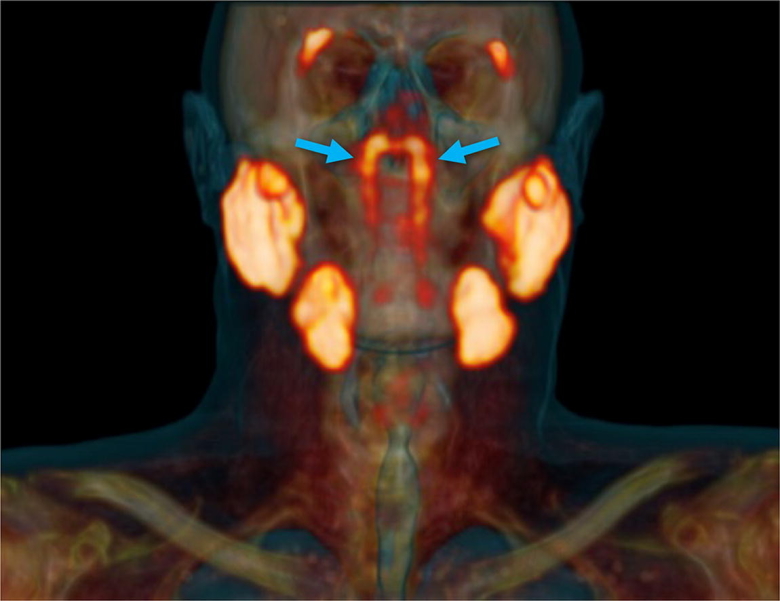

Голландские ученые обнаружили скрытый внутри головы человека орган, напоминающий набор слюнных желез, неизвестный ранее науке. Открытие было сделано случайно: в ходе контрастной томографии с введением в кровь онкологических больных радиоактивной глюкозы.

При обследовании сотни пациентов с раком простаты с помощью нового сканера PSMA PET/CT радиологи и онкологи обнаружили нечто странное. У людей три пары больших слюнных желез – околоушные, подчелюстные, подъязычные. «Но не в этом месте, – объясняет открытие радиолог-онколог Воутер Фогель из Нидерландского института рака. – Слюнные железы в носоглотке микроскопически малы: около тысячи их равномерно распределены по слизистой оболочке. Поэтому представьте себе наше удивление, когда мы увидели на снимках эти железы».